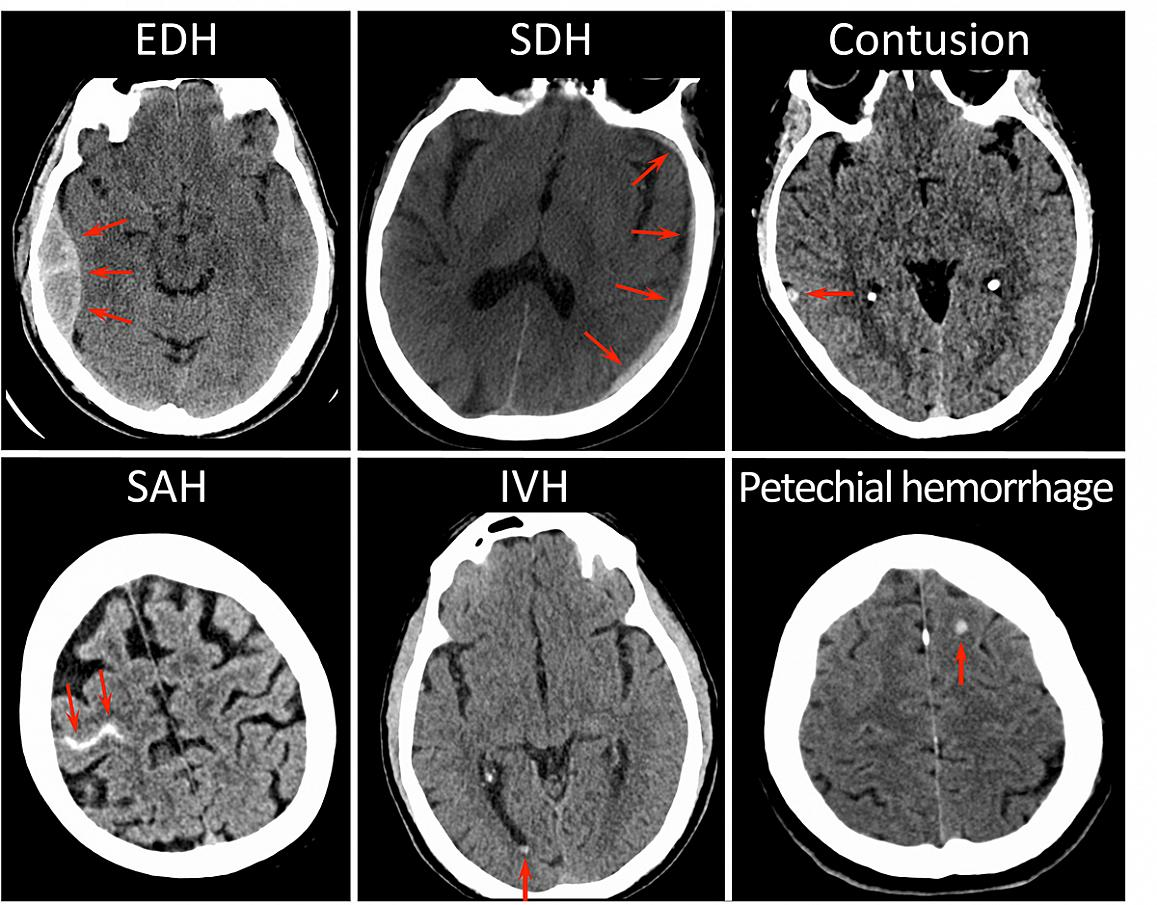

The researchers identified three distinct sets of patterns on the CT scans, indicating different types of damage after head injury which were associated with various outcomes. The results suggest that contusion (bleeding into brain tissue), subarachnoid hemorrhage (bleeding into the cerebrospinal fluid over the brain), subdural hematoma (bleeding between the brain and the thick covering over the brain), and intraventricular hemorrhage (bleeding into the fluid filled spaces in the center of the brain) were associated with worse outcomes 12 months after injury. Epidural hematoma, which describes bleeding between the skull and outer brain covering known as the dura, was associated with incomplete recovery at two weeks and three months, but was not linked to negative longer-term outcomes.